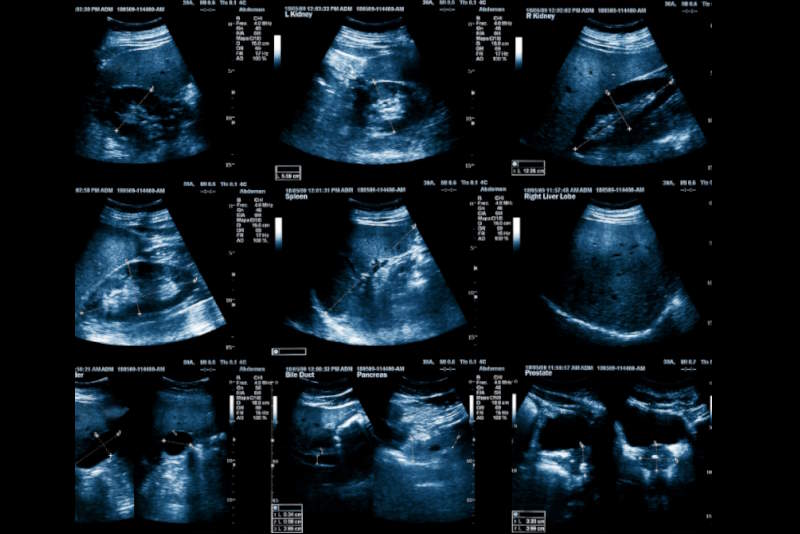

Presso il nostro centro diagnostico , l’ecografia viene eseguita con macchinari avanzati che garantiscono immagini ad alta risoluzione e analisi precise, per fornire referti chiari e utili alla pianificazione di trattamenti mirati. I nostri radiologi specializzati lavorano in collaborazione con ortopedici e fisioterapisti per offrirti un percorso diagnostico completo.

Durante l’esame, il medico applicherà un gel sull’area da esaminare e utilizzerà una sonda ecografica per ottenere le immagini in tempo reale. La durata dell’esame è generalmente tra i 15 e i 20 minuti e non presenta alcun dolore.